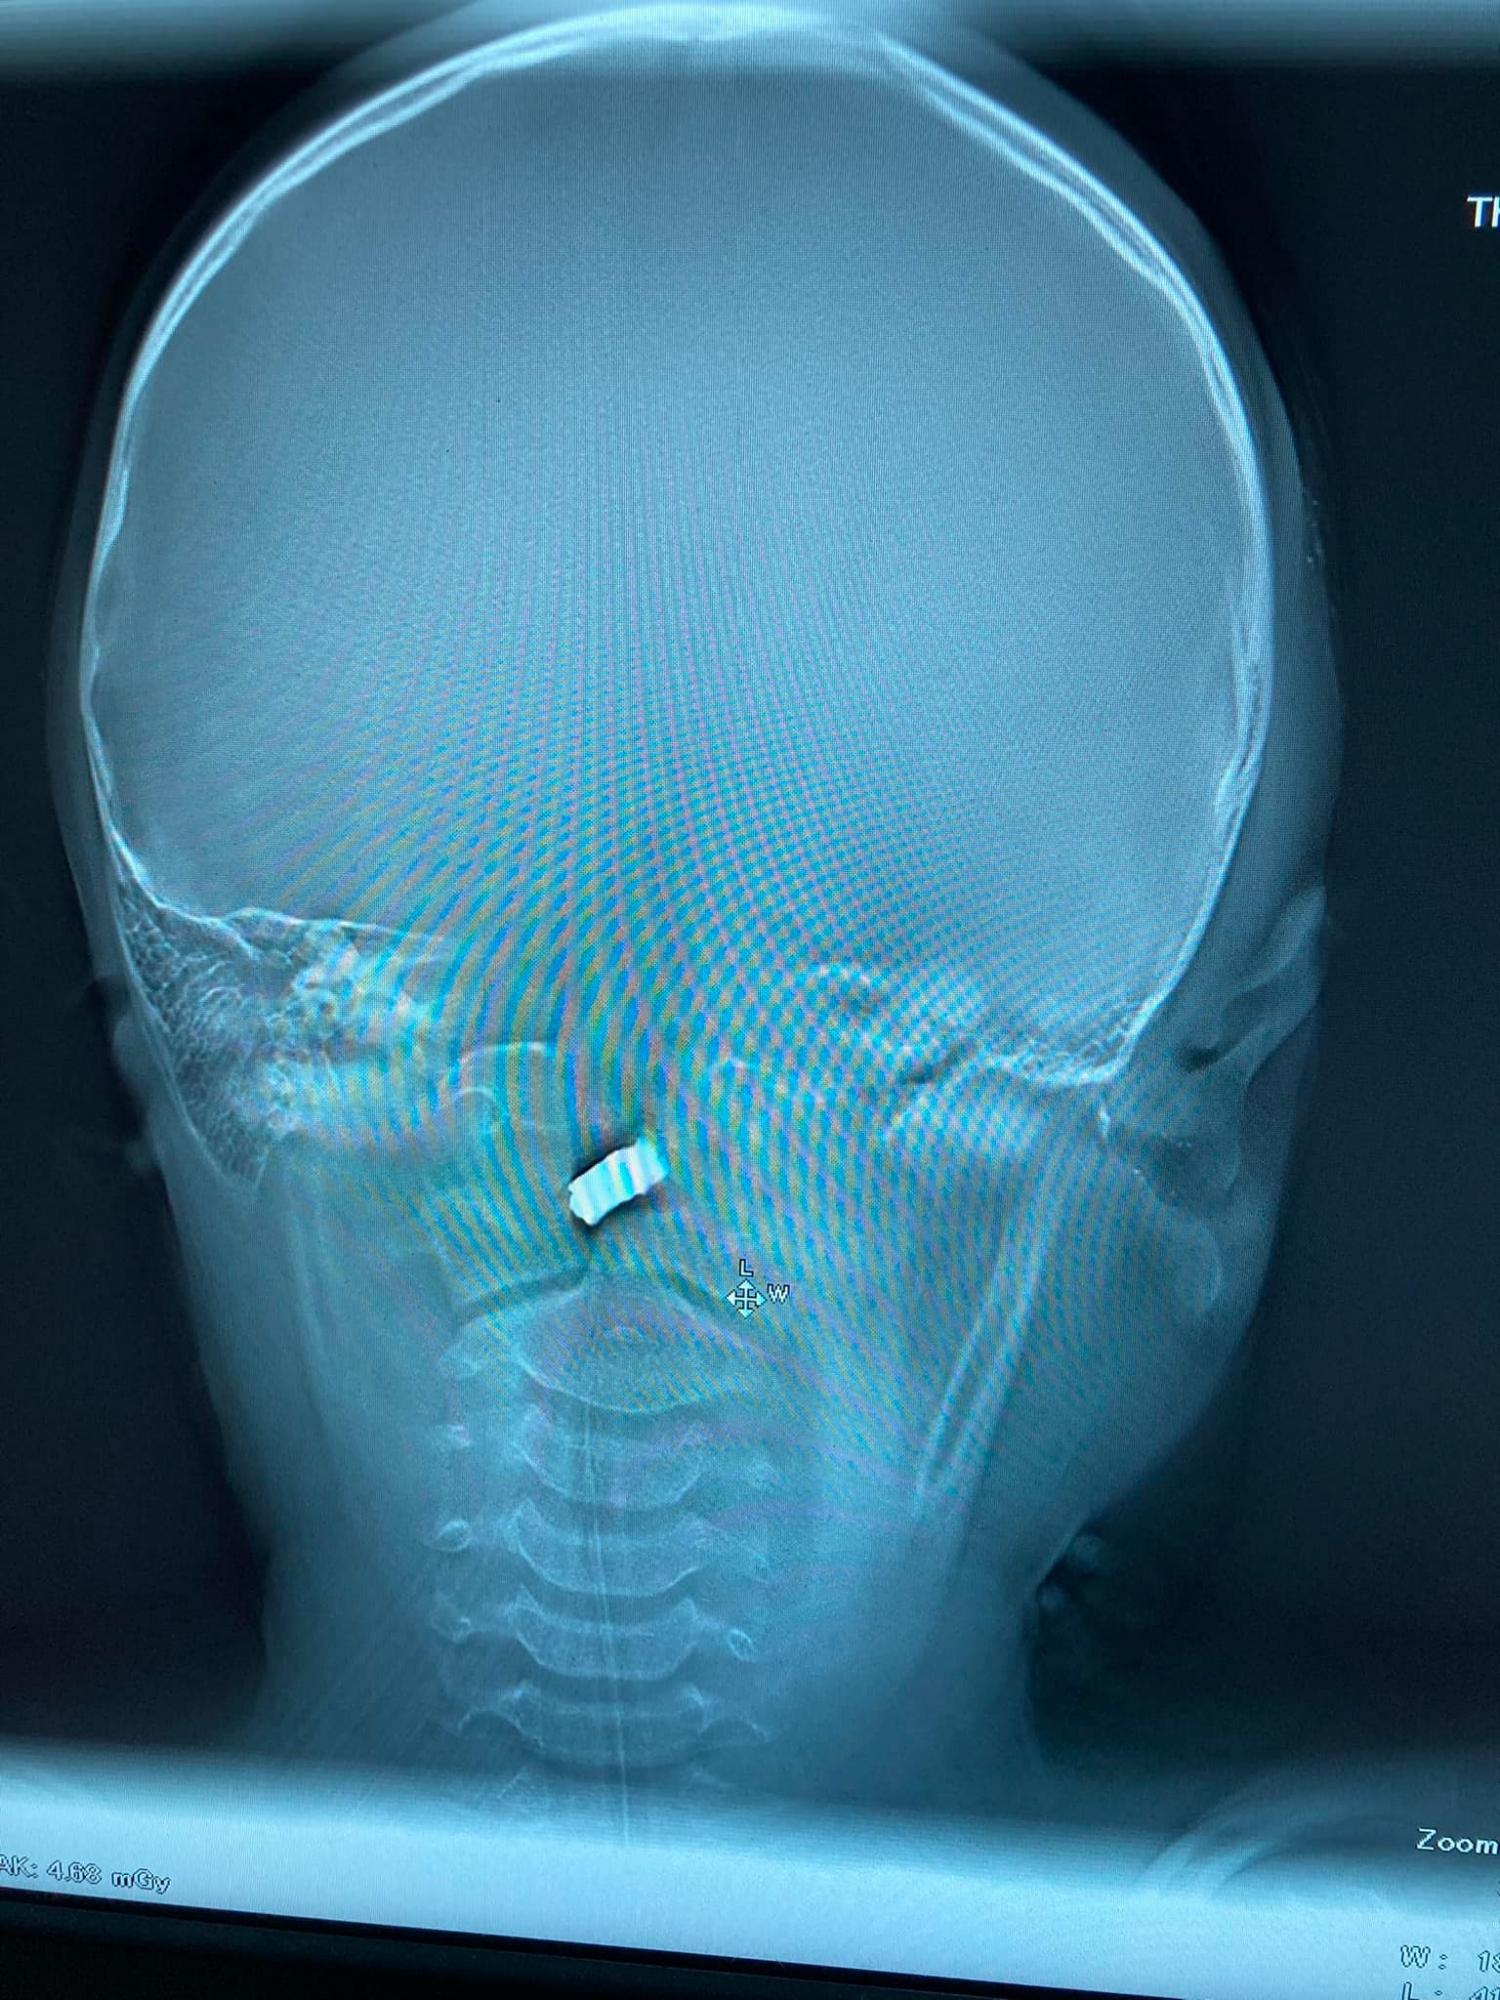

08:00 У Центрі дитячої нейрохірургії лікарі на чолі з Олександром Духовським рятують десятирічного хлопчика, в голову якого влучив уламок російського снаряда.